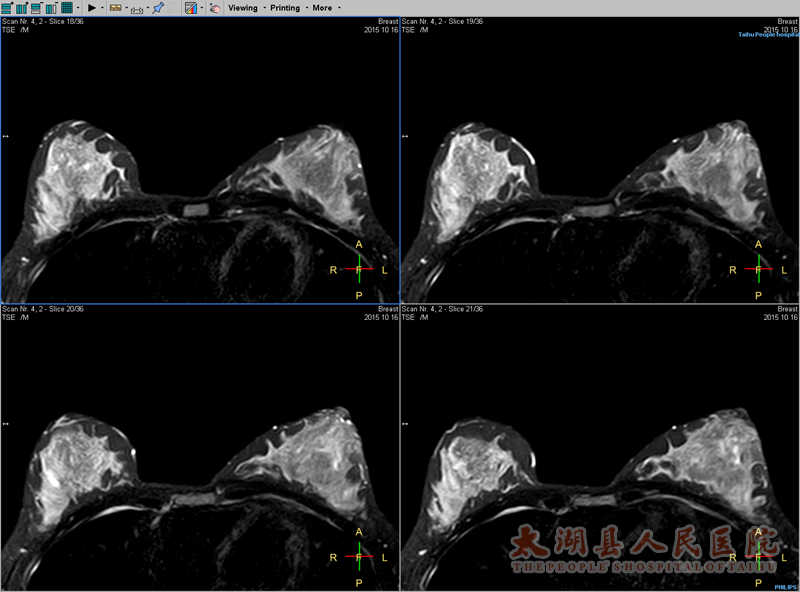

乳腺动态增强(DCE-MRI-1+6)、动态增强曲线(DCEmax